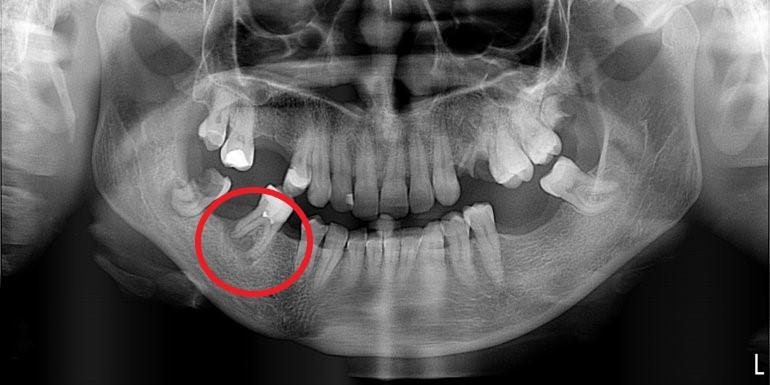

Leczenie kanałowe jest leczeniem skutecznym. Prawidłowe leczenie kanałowe sprawia, że ząb przestaje być ogniskiem zakażenia, a tkanki wokół goją się. Wyleczenie zęba powoduje, że przyczyna choroby tkanek około zębowych [na RTG widzimy jedynie chorobę kości] zostaje usunięta. Eliminacja przyczyny choroby umożliwia gojenie się zmian chorobowych.

Na poniższych zdjęciach RTG – WIDAĆ GOJENIE ZMIAN ZAPALNYCH KOŚCI.

Nie jest prawdą, że leczenie kanałowe w każdym przypadku jest szkodliwe. Ogniskami zakażenia są zęby martwe, nieprzeleczone kanałowo, zęby z nieprawidłowym leczeniem kanałowym i to właśnie one są zagrożeniem i powinny być eliminowane.